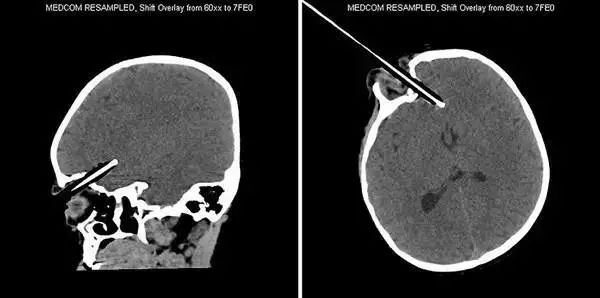

7、这名不幸的患者被一根撬棍刺穿头部。